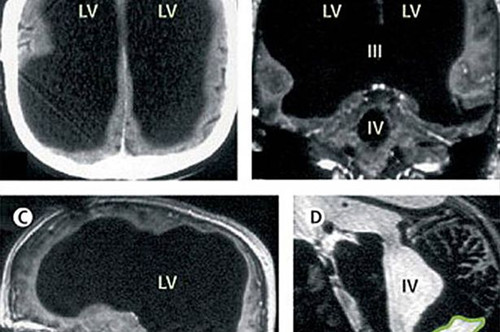

著名医学杂志《柳叶刀》披露,2007年,法国一名男子曾因腿部疼痛去医院检查,医生却找不出病根。在对其进行了全身体检后才发现,原来这名男子的腿疼是由脑部病变引起的,而该男子的大脑只剩下正常人大脑体积的一半都不到了,他左右半脑上的额叶、顶叶、颞叶及枕叶都萎缩了。

在对这名男子的病史进行详细调查后发现,原来他童年时患有后天脑积水症。但在他14岁时,经历了分流术,随后的30年,这名男子和家人都以为完全康复了。但其实他的大脑还是在病变,最终,脑内的积水损坏了脑组织,导致其大脑50%至75%的部分都消失了。